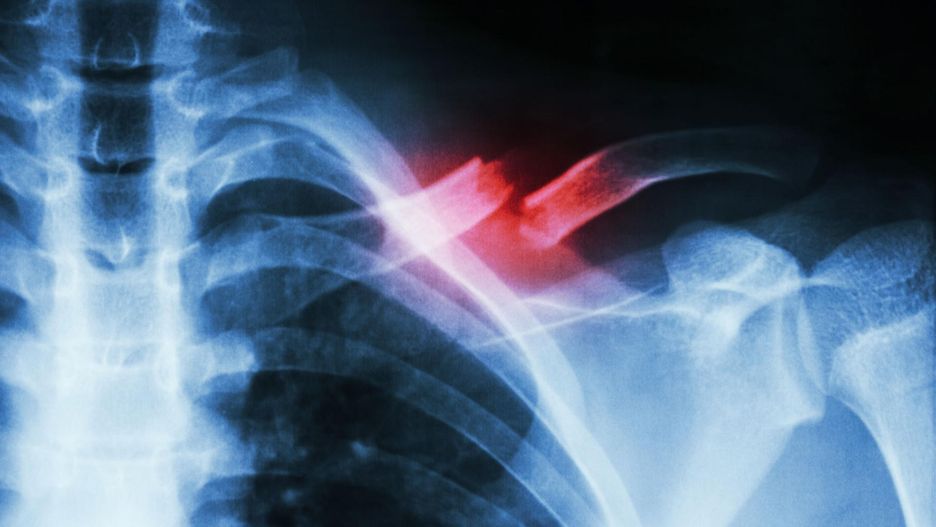

Złamanie obojczyka - postępowanie, leczenie, rekonwalescencja, powikłania

Złamanie obojczyka najczęściej powstaje jako uraz pośredni spowodowany upadkiem na wyciągniętą rękę lub bark. Ten typ urazu jest stosunkowo częsty u noworodków podczas porodu. W miejscu złamania kości pojawia się ból, obrzęk, trudno unieść rękę. Po tym, jak obrzęk ustąpił, można wyczuć złamanie przez skórę. Pacjent może mieć mdłości, zawroty i tak zwane mroczki przed oczami. Pęknięcie kości następuje przeważnie w miejscu, w którym obojczyk wygina się do przodu. Rzadko dochodzi do uszkodzenia splotu barkowego i tętnicy podobojczykowej.

Standardowa metoda diagnozowania złamania obojczyka polega na wykonaniu zdjęcia rentgenowskiego, jednak w przypadku dzieci bardziej efektywna może być tomografia komputerowa. Ponadto lekarz sprawdza, czy nerwy i naczynia krwionośne nie uległy uszkodzeniu. Takie obrażenia są rzadkie, ale warto upewnić się, ponieważ wymagają one interwencji lekarskiej.